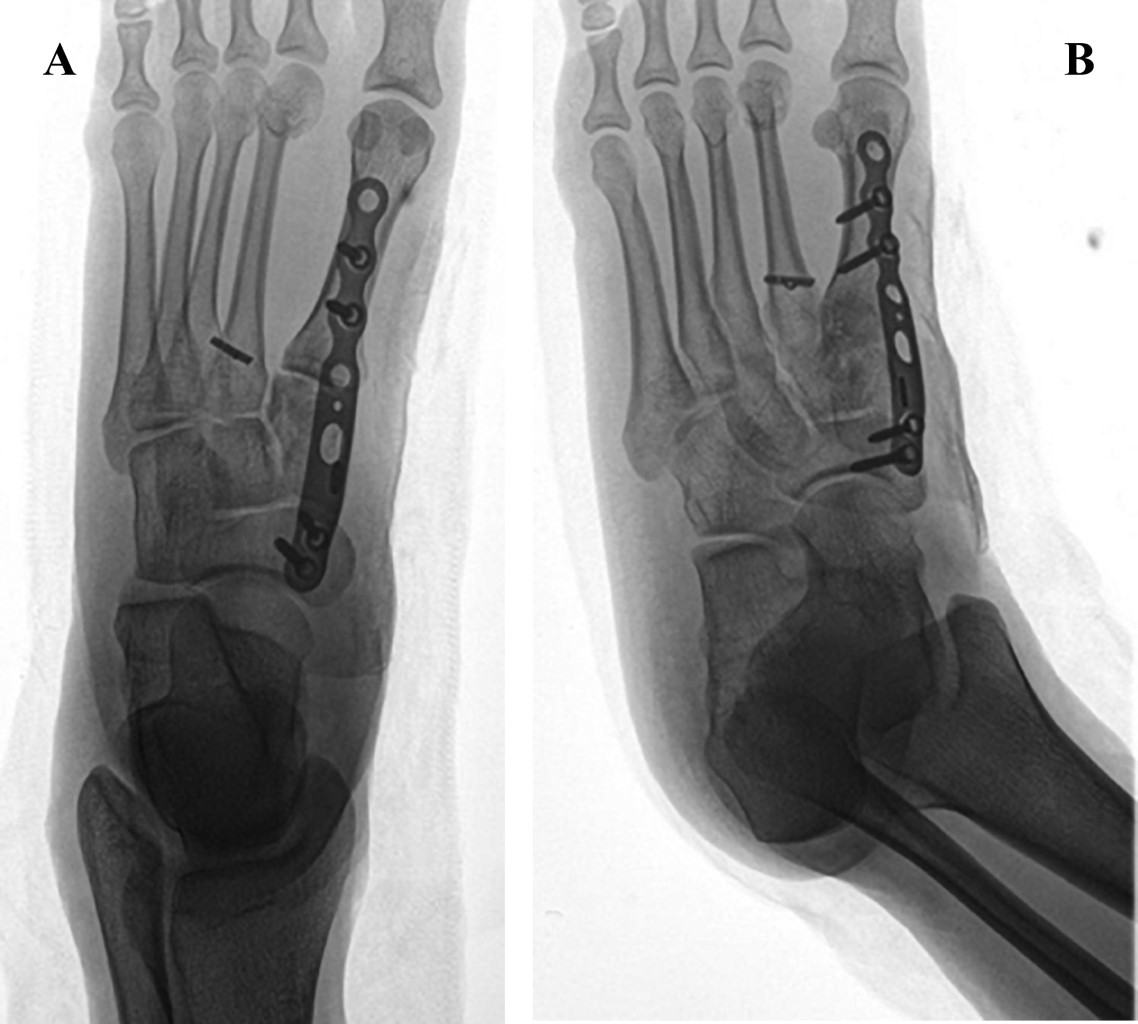

Figure 1